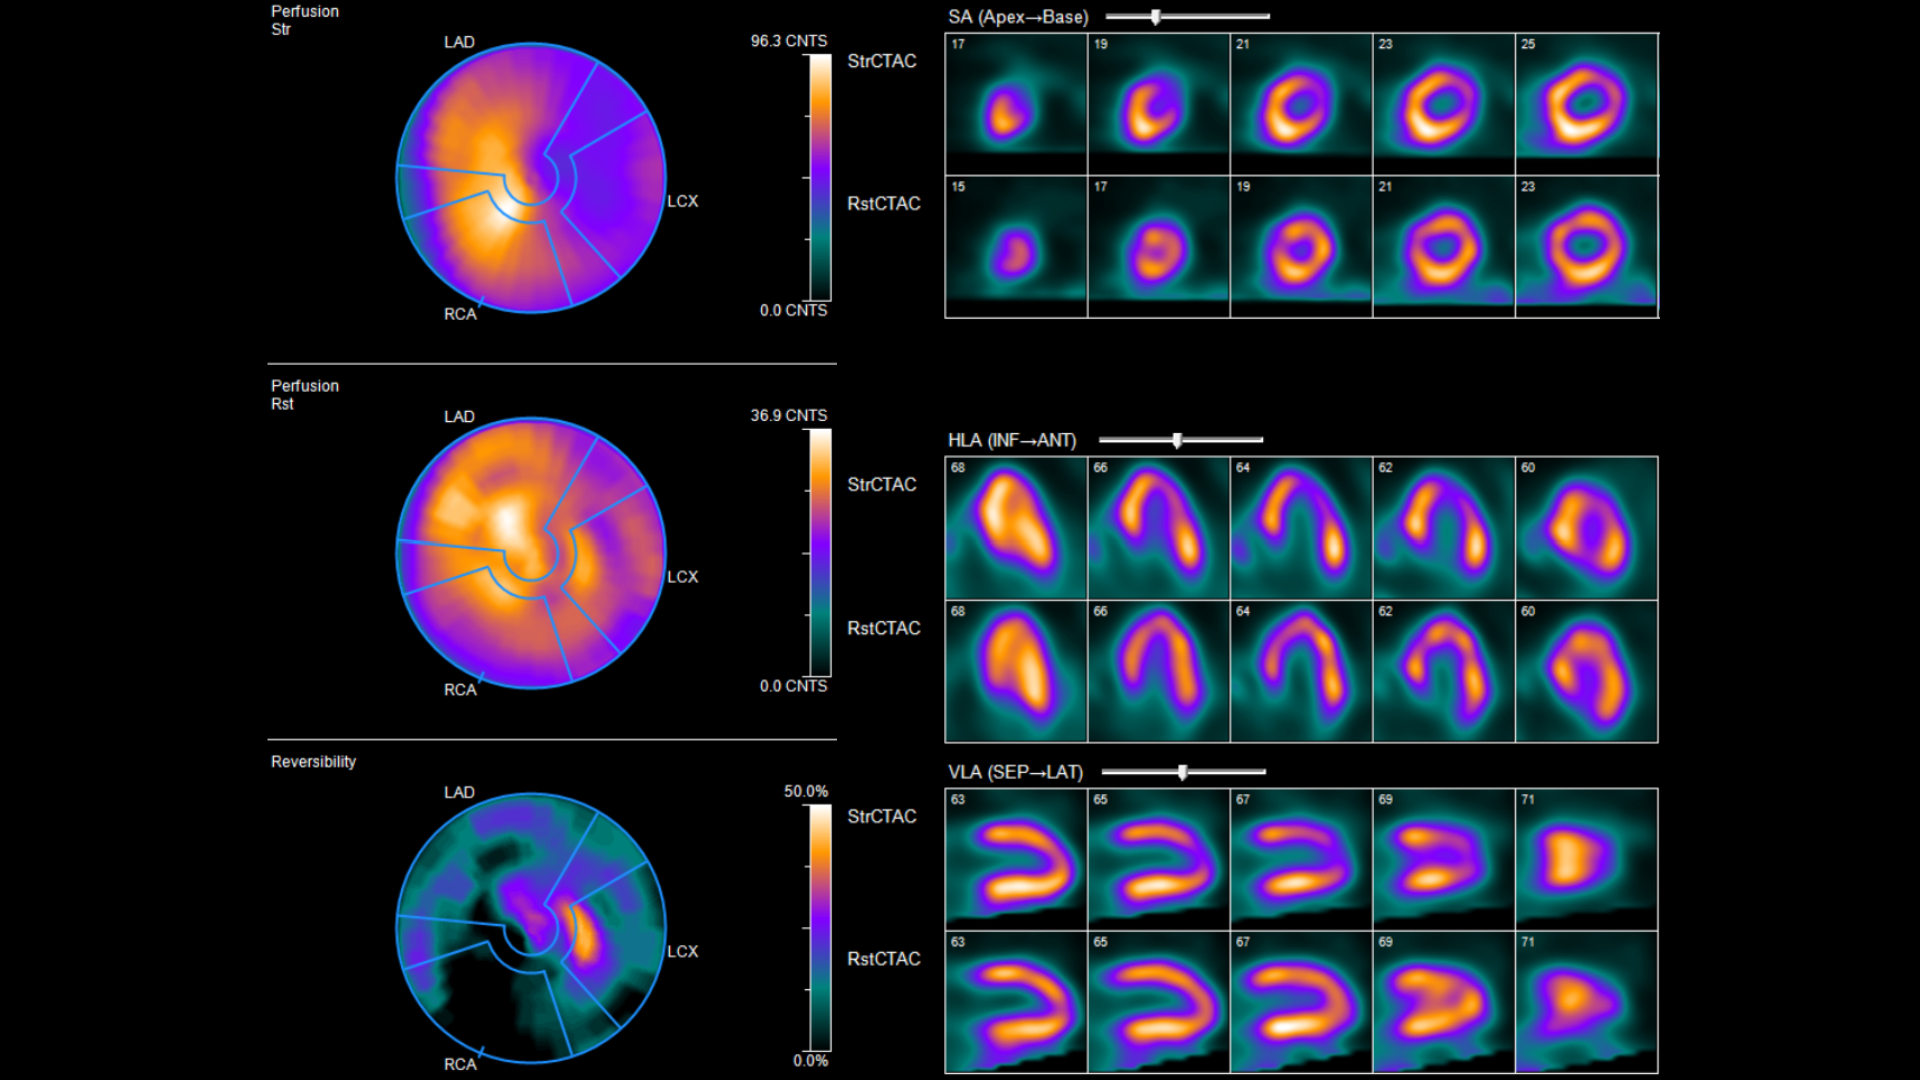

Nuclear Myocardial Perfusion Imaging

Nuclear myocardial perfusion imaging helps assess blood flow to the heart muscle and how well it is pumping. It is commonly used to investigate symptoms such as chest pain or shortness of breath, and to evaluate known or suspected coronary artery disease. This investigation is usually performed in two parts: a rest component and a stress component (either exercise or medication-induced). During each component, a small amount of injected radioactive tracer is taken up by the heart muscle, allowing it to be imaged with a specialised camera. Comparing rest and stress imaging helps nuclear medicine specialists understand how well blood reaches different areas of your heart and differentiates healthy muscle from that which is damaged or at risk of damage.

The test usually involves two parts: imaging at rest and imaging during stress. During the stress component, you may be asked to exercise on a bicycle. If exercise is not suitable, you may receive medication that temporarily dilates blood vessels in the body, as would occur during exercise. Your heart rate, blood pressure, and ECG will be monitored throughout. You may experience mild symptoms such as warmth and flushing, shortness of breath, or headache during the stress component; these usually pass quickly.

Whilst the images are being acquired, you will lie still on a scanning bed while a camera rotates around your chest.

You can usually return to your normal activities straight away. Drinking plenty of fluids after the test helps flush the tracer from your body. Close contact with children and pregnant women may need to be avoided for a few hours after the test; personalised advice will be provided where required.

A nuclear medicine specialist will review the images and send a report to your referring doctor, who will discuss the results with you and explain any next steps.